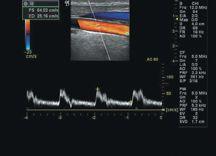

When Claude Bernard inserted a mercury thermometer into the carotid artery of a horse to measure blood temperature in 1844, little did he know he was laying the foundation for present day catheter angiography. Even though his practices were rudimentary compared to today’s standards, and it was not until 1929 that basic radiographic methods were implemented, he provided a stepping-stone into the current world of catheters and in turn, vascular imaging.